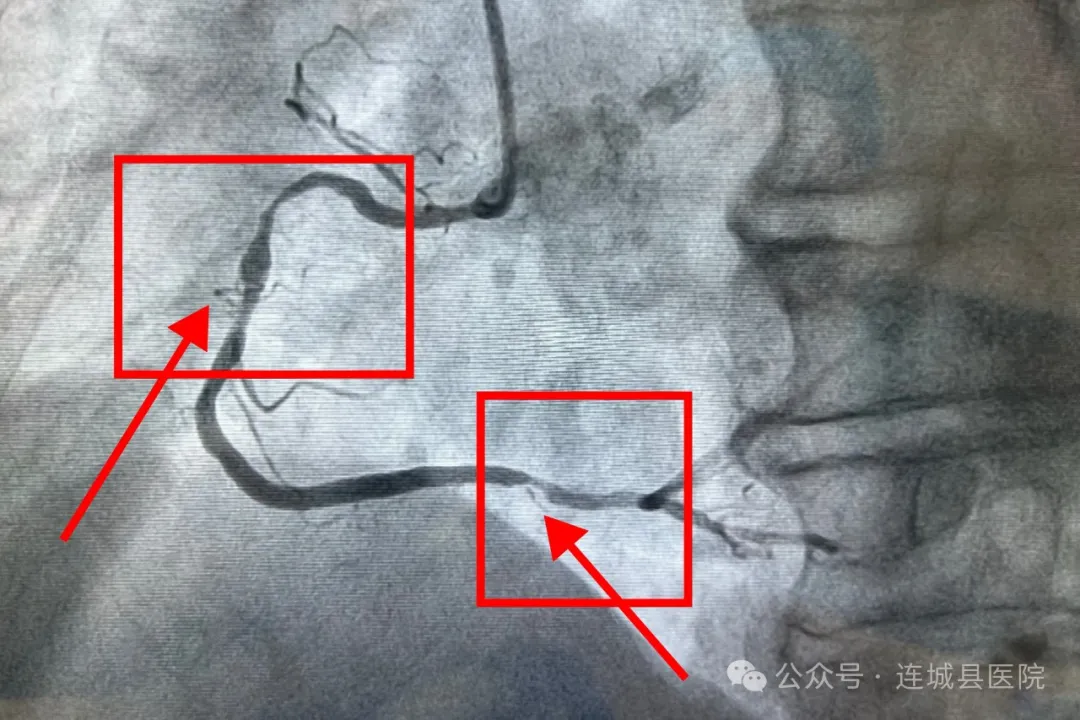

这位92岁的老人,近两个月深受胸痛、胸闷等症状的困扰,最终决定前来我院心内科就诊。面对这位高龄患者,心血管内科的王永福主任带领团队高度重视,进行了全面且深入的检查评估。从心肺功能到各项身体指标,都进行了详尽的分析。经过慎重讨论初步判断老人可能患有冠心病,并建议进行冠状动脉造影术以明确诊断进一步诊疗。在与患者家属进行了充分的沟通,详细解释了手术的必要性、风险和预期效果,并征得家属的同意后,王永福主任及其团队为老人制定了个性化的手术方案。

最终,在局部麻醉下,心内科医疗团队成功为老人实施了冠状动脉造影术。手术过程中,医疗团队展现出极高的专业素养和默契配合,每一个细节都处理得恰到好处,确保了手术的顺利进行。

造影结果显示

左主干+三支血管病变